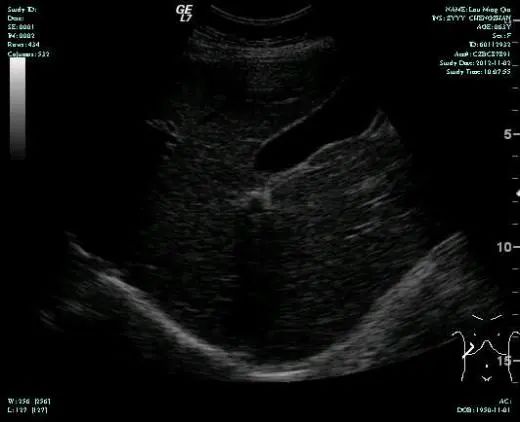

• 第三次FOLFOX+T方案后 B超提示肝转移灶消失

疗效评估:cPR

TOGA研究是第一个使用HER2抑制剂曲妥珠单抗治疗不能手术的局部晚期、复发或转移的HER2阳性胃癌患者的Ⅲ期临床研究。TOGA研究结果显示,IHC2+/FISH阳性或者IHC3+的患者与对照组相比,OS分别为16.0个月和11.8个月(HR为0.65)。曲妥珠单抗联合化疗显著提高了HER2阳性晚期转移性胃癌的治疗缓解率和总体生存率。2012年8月,曲妥珠单抗治疗HER2阳性转移性胃癌适应症在我国获批。对该患者进行病理切片会诊,幸运的是其HER2检测为阳性。随即进行靶向联合化疗治疗,三个周期后,肝转移灶消失,曲妥珠单抗治疗效果显著。九个周期的靶向治疗联合放化疗后,疗效评估cPR,随即行手术治疗。